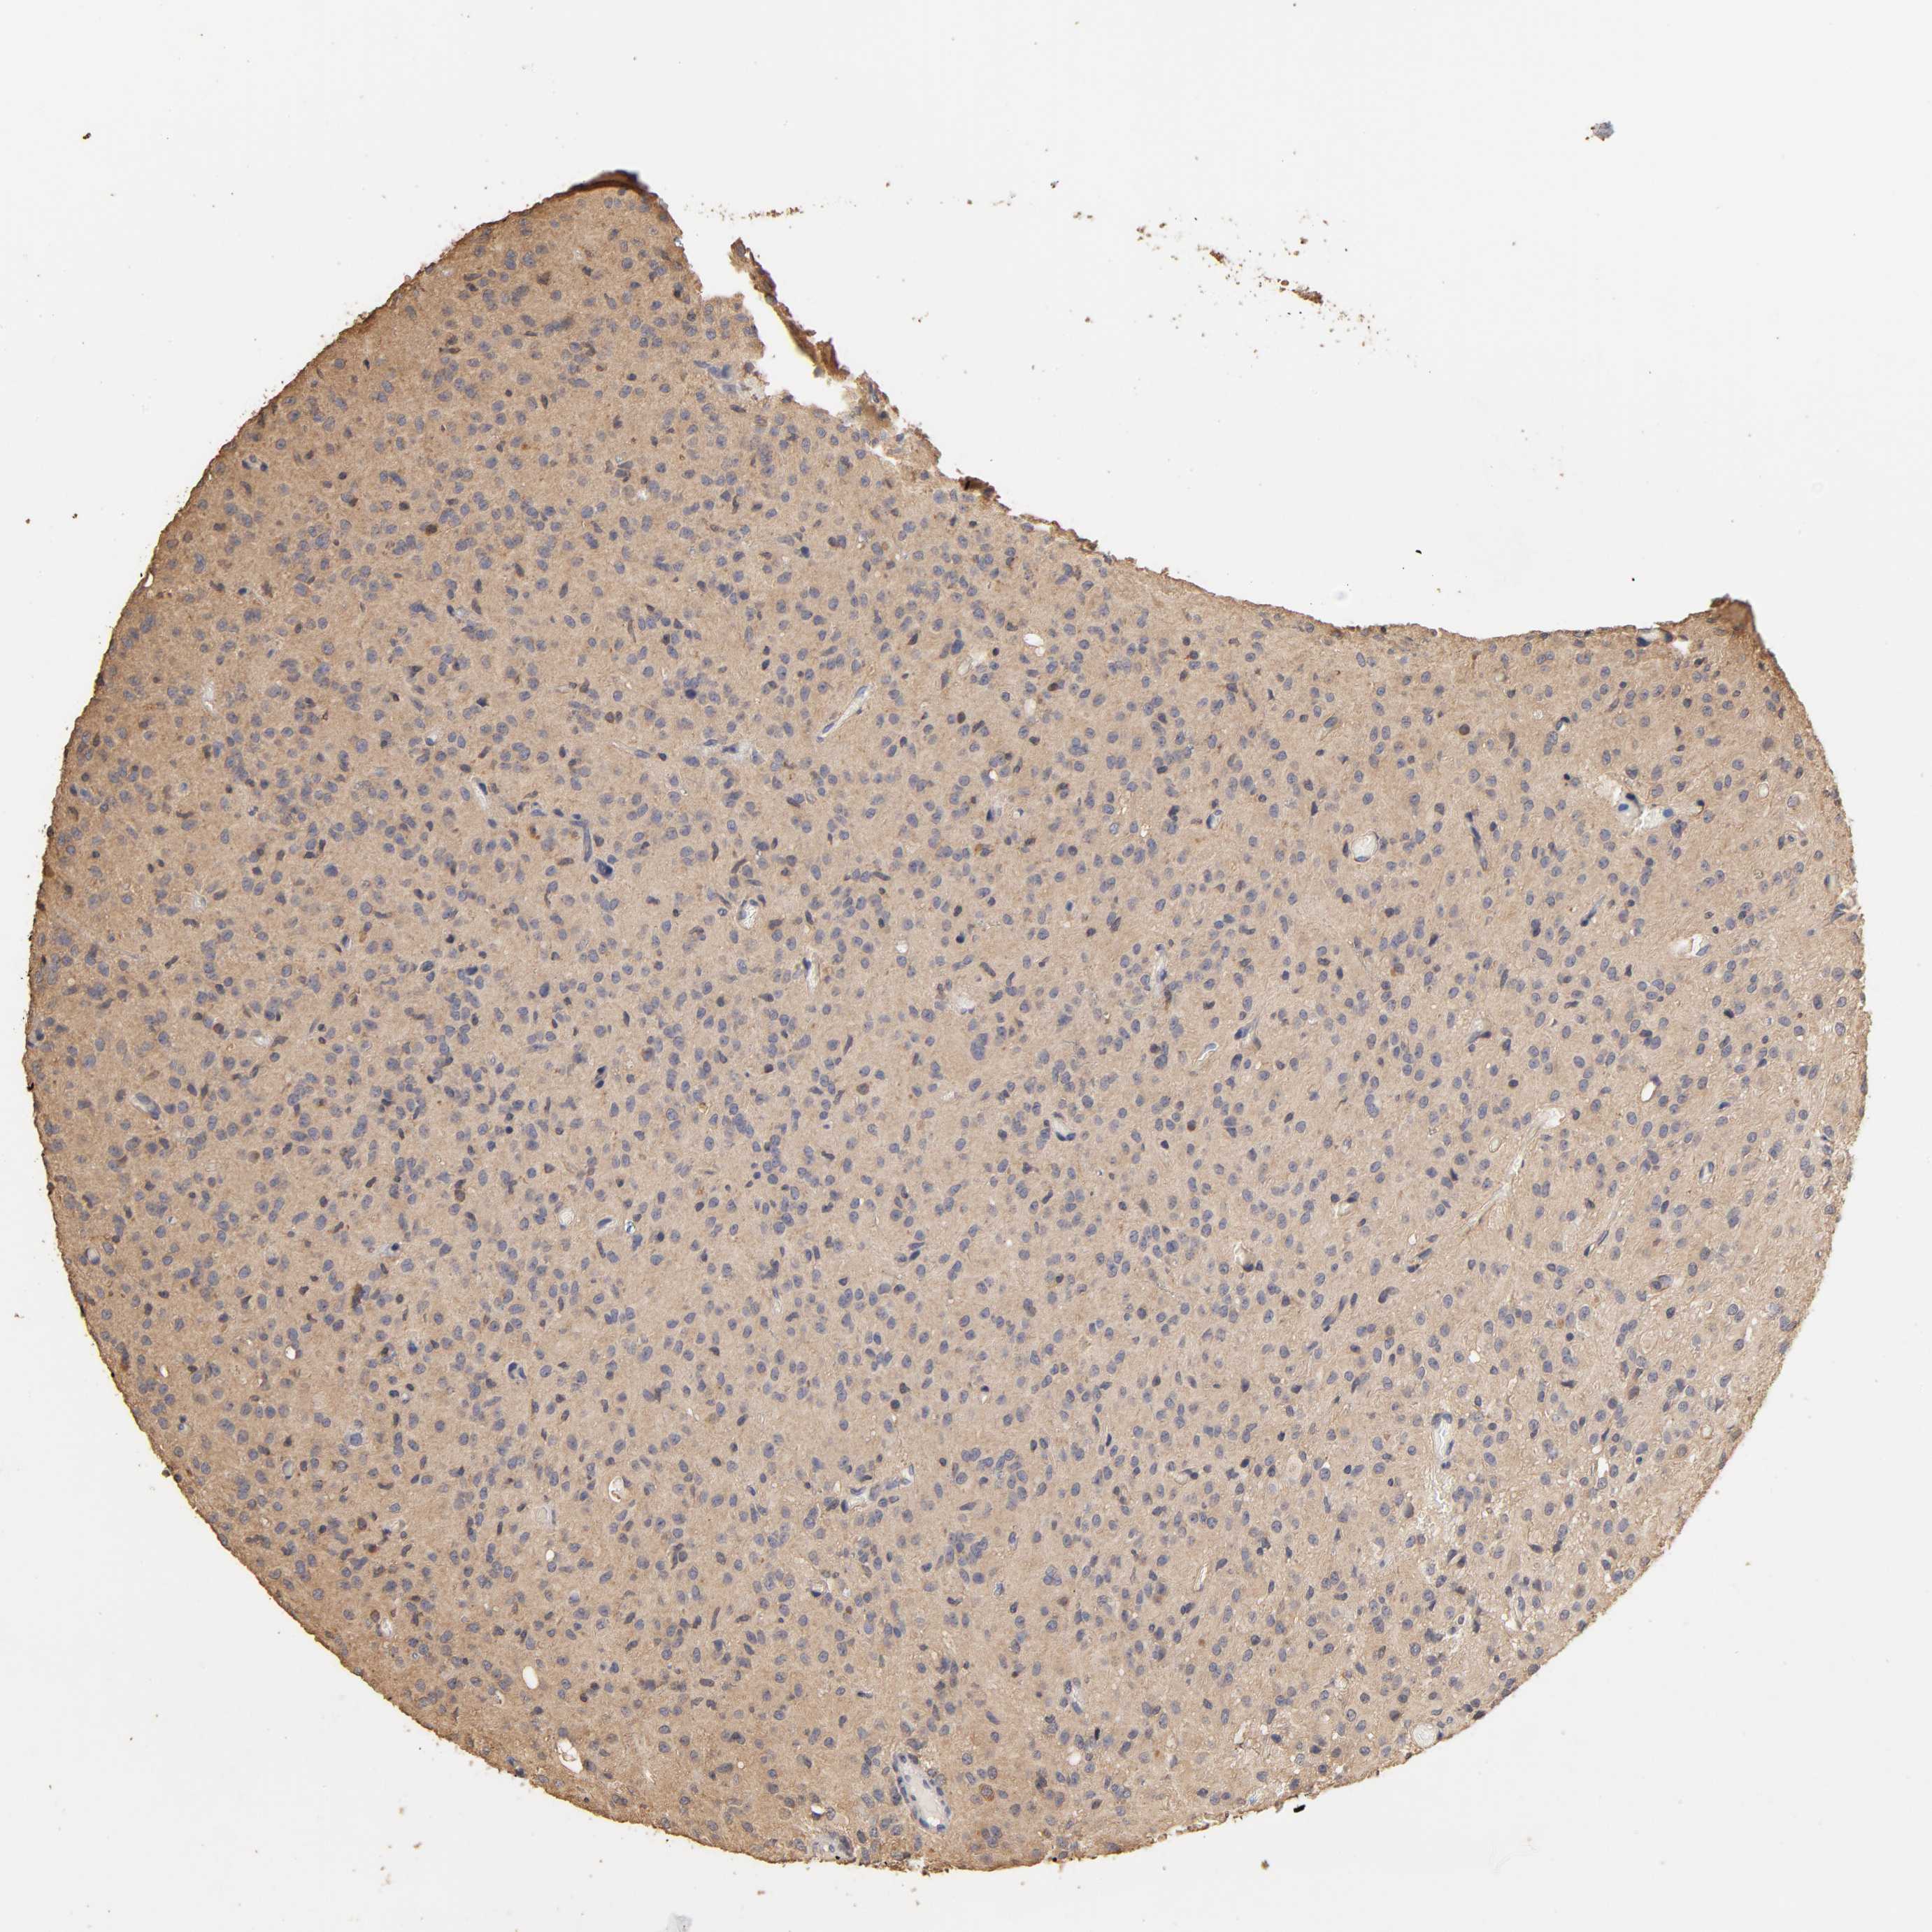

GLIOMA - Protein expressioni

A mouse-over function shows sample information and annotation data. Click on an image to view it in a full screen mode. Samples can be filtered based on level of antibody staining by selecting one or several of the following categories: high, medium, low and not detected. The assay and annotation is described here.

Note that samples used for immunohistochemistry by the Human Protein Atlas do not correspond to samples in the TCGA dataset.

Antibody stainingi

Antibody staining in the annotated cell types in the current human tissue is reported as not detected, low, medium, or high, based on conventional immunohistochemistry profiling in selected tissues. This score is based on the combination of the staining intensity and fraction of stained cells.

Each image is clickable and will lead to virtual microscopy that enables deeper exploration of all samples and also displays staining intensity scores, fraction scores and subcellular localization as well as patient and tissue information for each sample.

Antibody HPA003903

Antibody HPA072756

Antibody CAB026000

Staining

High

Medium

Low

Not detected

Intensity

Strong

Moderate

Weak

Negative

Quantity

>75%

75%-25%

<25%

None

Location

Nuclear

Cytoplasmic/membranous

Cytoplasmic/membranous,nuclear

Glioma, malignant, High grade

Glioma, malignant, NOS

Glioma, malignant, Low grade